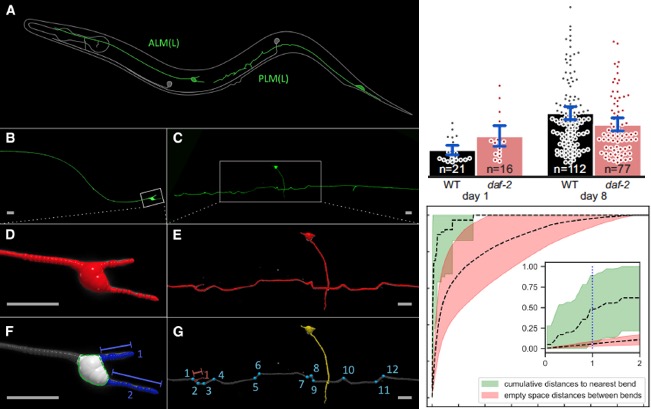

[2019] Max Hess, Alvaro Gomariz, Orcun Goksel, and Collin Ewald:

"In-vivo quantitative image analysis of age-related morphological changes of C. elegans neurons reveals a correlation between neurite bending and novel neurite outgrowths",

eNeuro 6(4), Jun 2019.

[2019] Max Hess, Alvaro Gomariz, Orcun Goksel, and Collin Ewald:

"In-vivo quantitative image analysis of age-related morphological changes of C. elegans neurons reveals a correlation between neurite bending and novel neurite outgrowths",

eNeuro 6(4), Jun 2019.

@article{Hess_in-vivo_19,

author = {Max Hess and Alvaro Gomariz and Orcun Goksel and Collin Ewald},

title = {In-vivo quantitative image analysis of age-related morphological changes of C. elegans neurons reveals a correlation between neurite bending and novel neurite outgrowths},

journal = {eNeuro},

year = {2019},

volume = {6},

number = {4},

doi = {10.1523/ENEURO.0014-19.2019}

}

[2024] Alina C. Teuscher, Cyril Statzer, Anita Goyala, Seraina A. Domenig, Ingmar Schoen, Max Hess, Alexander M. Hofer, Andrea Fossati, Viola Vogel, Orcun Goksel, Ruedi Aebersold, and Collin Y. Ewald:

"Longevity interventions modulate mechanotransduction and extracellular matrix homeostasis in C. Elegans",

Nature Communications 15(276), 2024.

[2024] Alina C. Teuscher, Cyril Statzer, Anita Goyala, Seraina A. Domenig, Ingmar Schoen, Max Hess, Alexander M. Hofer, Andrea Fossati, Viola Vogel, Orcun Goksel, Ruedi Aebersold, and Collin Y. Ewald:

"Longevity interventions modulate mechanotransduction and extracellular matrix homeostasis in C. Elegans",

Nature Communications 15(276), 2024.

@article{Teuscher_longevity_24,

author = {Alina C. Teuscher and Cyril Statzer and Anita Goyala and Seraina A. Domenig and Ingmar Schoen and Max Hess and Alexander M. Hofer and Andrea Fossati and Viola Vogel and Orcun Goksel and Ruedi Aebersold and Collin Y. Ewald},

title = {Longevity interventions modulate mechanotransduction and extracellular matrix homeostasis in C. Elegans},

journal = {Nature Communications},

year = {2024},

volume = {15},

number = {276},

doi = {10.1038/s41467-023-44409-2}

}